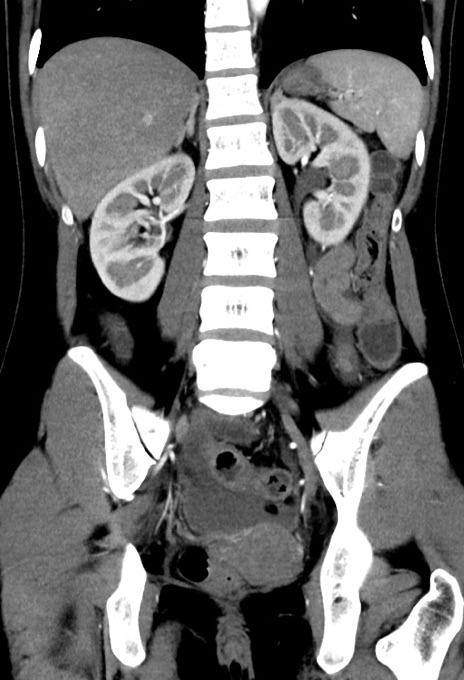

症例17(冠状断像)

【症例】20歳代女性

【主訴】嘔吐、下腹部痛

【現病歴】昨日夕食後に嘔吐し下腹部痛が出現。本日になっても嘔吐持続し改善しないため来院。

【身体所見】意識清明、BT 37.2℃、BP 108/67mmHg、腹部:平坦、やや硬、下腹部正中から右にかけて圧痛あり、反跳痛軽度あり、tapping pain(+)。

【データ】WBC 13600、CRP 14.94